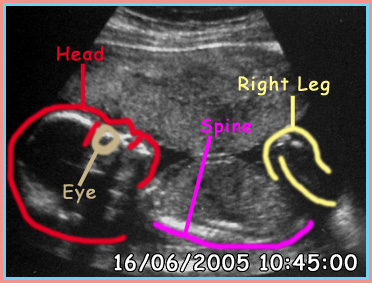

I have also marked out each section on a second picture showing you what is what, as they can be confusing to look at.

Labels of the Scan

Wk 20 - The Scans 2 the return

Well now we have hit the halfway mark we can show you the all NEW Junior scans. We must thank the scanner type person at Burnely General for the nice things and also being a good friend, Christine, Thanks lass.

Also we had a great time watching Jr. kick Vic's bladder many times too. At one point Jr. even looked at us and we could see the WHOLE skull and if we got a photo of that I may have had something to use to make up a face... Shame. As you may see on the third one the head is drawn with Jr's mouth open, this is due to the fact we saw Jr. drinking the fluid that surround the baby. You can even see the black lump in the head area that is the back of the mouth in which the liquid is held. The funniest bit was we had to wait till Jr's bladder was full before we were allowed to leave, and it took ages, also the bladder once full was SO small. No bigger than the lower bright spot on scan one at the elbow.

Ahh, another thing we got to watch Jr's heart from the top down. We so the four chambers and no hole in it, praise the Lord. Oh yes we did not ask for the gender of Jr. either.

The scans have been placed in order they have been taken.